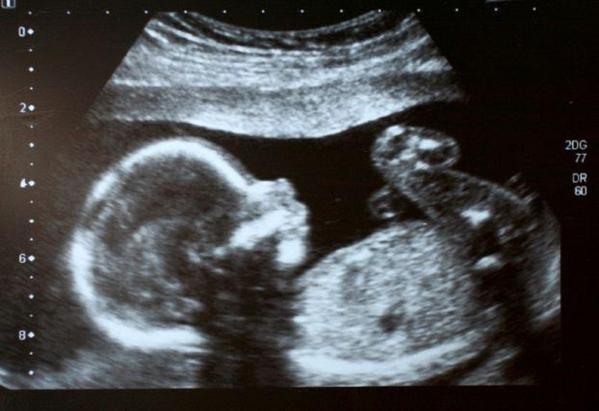

مسنة تحمل في رحمها جنيناً ميتاً منذ 50 عاماً

أظهرت فحوصات روتينية أجرتها جدّة تشيلية 92 عاماً، أنها تحمل في رحمها جنيناً ميتاً منذ 50 عاماً، وفق ما كشفته مصادر طبية، ذلك حسب مانشرته مواقع إخبارية.

واكتشف الجنين الذي كان في شهره السابع، ويزن كيلوغرامين، بعد إجراء تصوير بالأشعة.

ومات الجنين لأسباب غير محددة، وكانت المرأة تجهل أنها حامل في تلك الفترة.